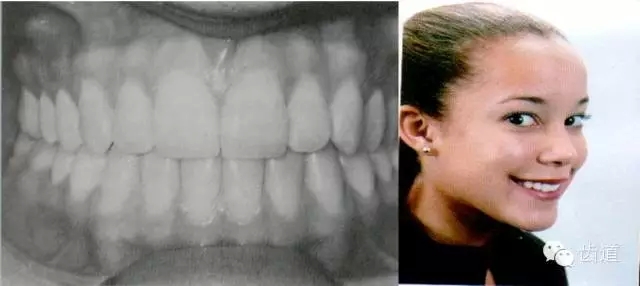

上頜6的近中頰尖正對下頜6的頰溝

上頜6的近中舌尖位于下頜6的中央窩內(nèi)

下頜6的遠中頰尖位于上頜6的中央窩內(nèi)

典型面形